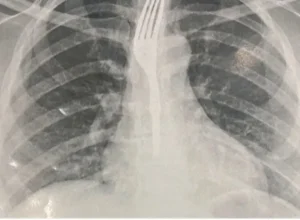

Uma ocorrência incomum mobilizou equipes de saúde em Guanambi na última sexta-feira (26). Uma mulher precisou de atendimento médico urgente após engolir um garf...